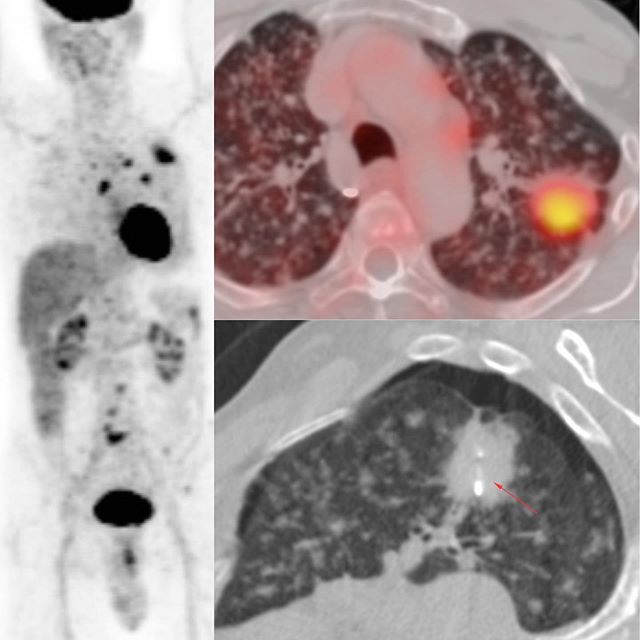

This is a 77-years old man who presented with Stage IV metastatic lung cancer. The PET CT scan showed a mass in the apico-posterior segment of the left upper lobe with extensive lung metastases.